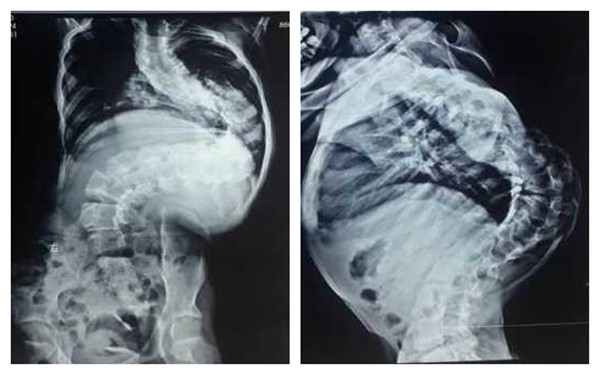

手术前X片

患者王某,女,13岁,十余年前无意间发现脊柱向侧后方弯曲,进行性加重,呈大驼背畸形,患儿家属辗转全国多家三甲医院就医,但均被告知风险及难度太大而放弃治疗。有人建议在网上搜索,于2015年7月才慕名到我院骨二科就医。接诊后,李浩鹏教授带领脊柱外科团队多次讨论病例,认为:患儿脊柱向外成角>160度(Cobb角超过160度),脊柱严重畸形、椎旁肌肉僵硬、胸廓畸形。如果采用直接手术矫形的方式,手术难度与风险极大。为了确保患儿安全及保护神经功能,最终决定运用渐进的方式进行治疗。首先采用头颅及双下肢骨牵引术,即在头顶两侧使用颅骨牵引架向上牵引,在双下肢胫骨踝上打克氏针向下牵引,通过上下两个方向同时逐渐牵引,将弯曲礓硬的脊体牵长、拉软,为手术做准备。在持续牵引2周后,胸廓畸形、椎旁肌肉僵硬等情况得到较大改善,身长由130增加到145厘米。牵引过程中,孩子基本是固定在床上,很痛苦,但为了手术的顺利进行,患儿和家长都在竭尽全力地配合。